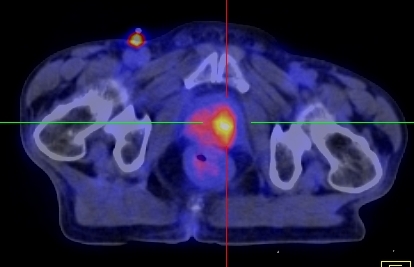

Hình dưới đây cho thấy giá trị của PET/CT trong phát hiện tổn thương tại tuyến tiền liệt.

Hình 1. Bệnh nhân Phan L. Th., nam, 75 tuổi, chẩn đoán: Ung thư tuyến tiền liệt. Trên hình CT, FDG-PET và FDG-PET/CT thấy khối u thùy trái tuyến tiền liệt tăng hấp thu FDG mạnh, max SUV=5,57.